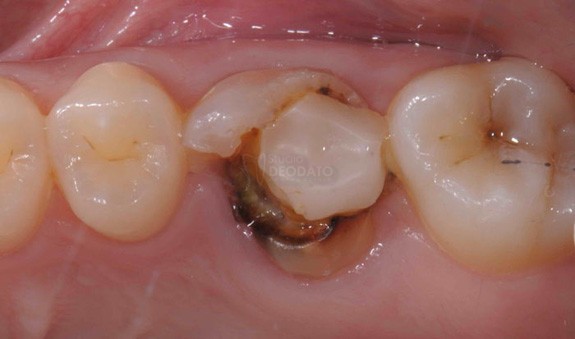

Immagine di ampia lesione cariosa

Esempio clinico di restauro diretto od otturazione in composito

Frattura dell’incisivo centrale e laterale risolti per mezzo di due restauri diretti in composito.